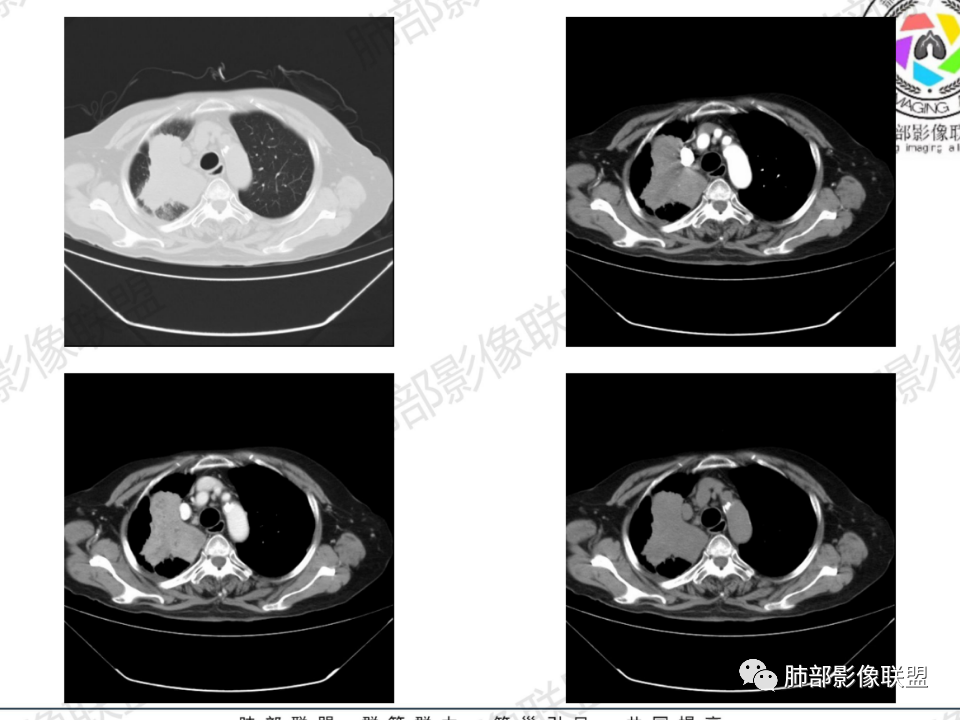

那个人:老年女性,亚急性病程,咳嗽发热。有垂体前叶功能减退,目前激素替代治疗,长期激素,量小,不知道累积量,没有目前激素水平指标。既往有淋巴结结核病史。肿瘤标记物Ca125升高。血沉升高,C反应蛋白轻度异常。影像,右肺上叶靠近肺门团块影,右肺门淋巴结钙化肿大,支气管狭窄,局部增厚,团块影外朝内改变,强化明显,血管破坏不明显,有粘液。和纵隔胸膜分界清楚,周围肺组织有斑片渗出影,右侧胸腔积液,考虑炎性?结核?支气管镜检查除外恶性飞鹰行动:老年患者,影像表现 右肺上叶占位性病变,边界清楚,有分叶征,内见细小钙化,右肺上叶支气管截断,增强病灶不均匀强化,病灶内有条状坏死区(扩张的支气管?),纵膈内未见增大淋巴结,考虑炎性病变,结核可能。一切∮随缘:右肺上叶实性肿块形态不规则,呈三角形,边缘分叶,边界伴有磨玻璃影,近段支气管未见明显显示,可能堵塞,病变平扫密度均匀,增强后可见低密度坏死无强化,周围略强化,右肺下叶散在结节。心包积液,及右侧胸腔积液,临床:有低热,低蛋白血症,肿瘤标记物高,考虑恶性:腺癌,神经内分泌癌(强化偏弱了),淋巴瘤,鉴别:结核红星:老年女性患者右肺上叶,肺门上区 分叶状肿块 ,右肺上叶支气管显示不清,增强扫描肿块,中等程度强化可见小斑片状坏死区,病灶内部可见斑点状钙化灶,病灶周围可见斑片状及小斑点状影,纵膈淋巴结增大,其他区域,胸膜下可见斑点状钙化。考虑肉芽肿性病变,结核的可能性大。老年患者最排除肿瘤性病变腺癌。土娃:右上肺不规则肿块影,边缘分叶,边界磨玻璃影欠清,病灶分叉状,内见点状钙化影及坏死灶,支气管堵塞,病灶增强强化不明显。考虑瘤样结核,鉴别淋巴瘤。张小兵:老年女性,亚急性病程,右肺上叶见不规则肿块,边缘平直凹陷为主,周围GGO边界不清,内见点状钙化及坏死灶,增强持续性渐进强化,右侧少量胸腔积液,双肺门及纵隔肿大淋巴结伴钙化,综合考虑慢性炎症。saf:老年患者,影像表现 右肺上叶占位性病变,边界清楚,有分叶征,增强病灶明显不均匀强化,纵膈内未见增大淋巴结,考虑炎性病变,结核可能。小兜:老年女性,咳嗽喘息一月,发热三天,肿瘤标志物升高,长期激素替代治疗。CT示右肺上叶近肺门不规则实变影,周围伴磨玻璃影,增强持续性渐进强化,内部血管破坏不厉害,内部可见多发条形低密度灶,右侧胸腔可见少量积液,双肺门及纵隔可见钙化淋巴结,考虑为炎性病变,结核可能玫:女,79咳嗽,喘息一月,发热三天入院,右肺上叶不规则形软组织密度肿块影,边界清晰,边缘见分叶及细短毛刺,病灶内见点状钙化影及稍低密度区,病灶边缘呈磨玻璃样改变,增强扫描,病灶呈不均匀性强化,考虑炎性病变,鉴别鳞癌。大雄:老年女性,既往诊断淋巴结结核,提示已治愈,近2年服用激素,诱导结核复燃→发热;纵隔肺门淋巴结肿大钙化,压迫支气管,右肺上中下叶支气管均狭窄→喘息咳嗽;尖段支气管受累闭塞→肺不张、支气管粘液栓;累及胸膜,结核性胸膜炎并胸水→右侧胸痛;实验室,血沉快,CA125高,低蛋白,符合;下一步,支气管镜尖段支气管刷检抗酸染色周太狼:老年女性,亚急性病程,肿瘤标志物升高。CT示右肺上叶尖段不规则肿块影,有分叶、收缩,周围伴磨玻璃影,增强渐进强化,内部可见多发条形低密度灶,右侧胸腔及心包少量积液,纵隔内淋巴结稍增大。倾向于恶性病变,肺癌伴阻塞性炎变可能。丽:老年女性,右肺上叶不规则软组织肿块,边缘清晰,内密度不均,可见点状钙化及粘液栓,周围可见片状高密度影,增强后均匀强化,内多发低密度,纵膈多发钙化淋巴结,考虑结核可能大,建议结合支气管镜检查除外肿瘤宇宙:右胸廓缩小,右肺上叶团块影及不张,平直边,周围磨玻璃影,纤细胸膜牵拉,上叶尖段支气管堵塞,明显延迟强化,可见支气管粘液栓,两肺门钙化淋巴结,右侧胸水,考性炎性肉芽肿,鉴别腺癌王秀仙:右肺上叶肺门区肿块,上叶支气管开口阻塞,形态不规则,密度不均,内可见支气管粘液栓及多发小灶性坏死,周围磨玻璃影边缘模糊,渐进强化,右侧胸腔积液、胸膜钙化,考虑炎性肉芽肿性病变,慢性炎症。鉴别鳞癌,结核。刘丹:老年女性,右肺上叶肿块伴钙化,右肺上叶支气管截断,增强后均匀强化,周边可见点片状模糊影,右侧胸腔积液,右肺门淋巴结增大,考虑占位并阻塞性炎症,肿瘤?结核?建议纤支镜检查。小飞:右肺上叶纵隔旁软组织肿块,边缘深分叶、长毛刺及毛刷样短毛刺,边缘磨玻璃影,磨玻璃边界模糊,支气管截断,平扫密度不均,可见点状钙化,增强不均匀明显强化,心影增大,心包积液,右侧胸腔积液,考虑恶性肿瘤,腺癌?秦化君:右肺上叶不规则分叶软组织密度肿块,边缘清晰,胸膜牵拉,周围花花草草,上叶尖段支气管阻塞,内可见点状钙化,增强后密度不均可见支气管粘液栓及坏死区,内见血管分枝。中间段及中叶,下叶支气管狭窄,壁见钙化。右肺门淋巴结肿大,右侧胸腔积液,心包粘连肥厚。考虑1右上肺恶性病变,鳞癌?2右肺多叶段支气管狭窄,考虑支气管内膜结核?3胸腔积液及肺门淋巴结肿大,转移?风儿:老年女性,右肺上叶肿块,形态不规则,外围大内带小,边缘分叶膨隆平直及毛糙,密度不均,内见支气管粘液栓及多发小灶性坏死,坏死边缘清晰 ,渐进强化,上叶尖段支气管阻塞,叶支气管壁有局限性增厚,邻近胸膜腔微积液;纵隔及双肺门淋巴结肿大,部分钙化,右侧胸腔积液、心包积液、胸膜钙化,考虑炎性,肉芽肿性结核可能性大。鉴别鳞癌,女性及血供均不支持;腺癌,坏死边界太清晰。流心明智:老年女性,79岁,咳嗽、气短1月,发热3天。胸CT:右肺上叶见不规则肿块,边缘有膨隆、有平直凹陷,周围GGO边界不清,病灶内见点状钙化、粘液栓,尖段支气管未见,增强持续性渐进强化,右侧少量胸腔积液,双肺门及纵隔肿大淋巴结伴钙化,肺动脉增粗。考虑:右上叶尖段堵塞并慢性炎症,支气管TB并结石?鉴别Ca

右肺体积小,提示既往结核

支气管影

前,后段都在,没有堵塞

支气管壁增厚,周围磨玻璃边界不清,提示炎症。胸膜下钙化符合结核

结核是肯定有。现在最大问题是尖段

近端显示不清,但是远端是粘液栓,可以认为是还行的

如果是近端鳞癌,远端应该会堵塞,不会整个肿块里面还有较为通畅的支气管

这个区域我们看到密度与周围一致,并不是肺癌伴周围不张的感觉,所以鳞癌暂时是不支持的

临床信息:老年女性,亚急性病程,咳嗽发热。有激素使用史。既往有淋巴结结核病史。肿瘤标记物Ca125升高。血沉升高,C反应蛋白轻度异常。 影像所见:右侧胸廓相对狭小,右肺上叶不规则团块影贴附纵隔旁,轻度分叶,整体密度较均匀,偶见钙点。

相应上叶尖端及前段支气管开口未能追踪(阻塞),开口处见钙化。病灶渐进性强化,并衬托出较完整尖段及前段含液支气管影。支气管开口区域未见异常高密度强化(如类癌等)及相对乏血供区(如鳞癌)。病灶区未见液化坏死。右上纵隔及胸廓入口区未见病灶胸膜外突破(栽赃)。

纵隔及双肺门见钙化淋巴结。心包积液,右侧胸腔积液(提示存在活动新病灶)。双侧胸膜下见多发斑点状钙化,胸廓变形(提示存在结核基础病变可能)。 诊断意见:综上,右肺上叶块状影更符合继发性肺结核。 最后小结:既往诊断淋巴结结核,提示已治愈。近2年服用激素,可疑诱导结核复燃,也可引起发热。纵隔肺门淋巴结肿大钙化,压迫支气管,右肺上中下叶支气管均狭窄,所以引起喘息咳嗽。尖段支气管受累闭塞,导致肺不张、支气管粘液栓,出现条状无强化区。病变累及胸膜,导致结核性胸膜炎并胸水,引起右侧胸痛。实验室检查血沉快,CA125高,低蛋白,均符合结核。下一步,建议支气管镜尖段支气管刷检并抗酸染色。(本段摘自於雄老师精彩发言)